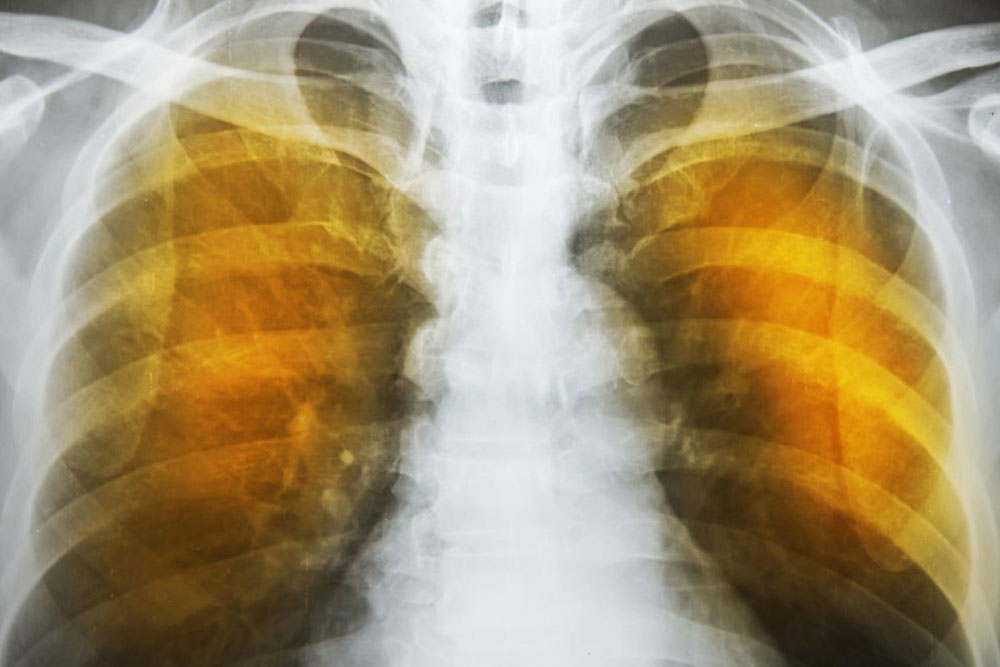

What is emphysema and what are its complications?

Emphysema is an oppressive respiratory disorder which results from the disintegration of the alveoli, i.e., the tissues where the interchange of gas with blood takes place. Destruction in any large scale will reduce the gas transfer area and the process of gas transfer itself, leading to oxygen starvation or hypoxia. When conventional treatment with bronchodilators, corticosteroids etc. have ceased to give relief, one has to resort to a method known as Long Term Oxygen Therapy or LTOT.